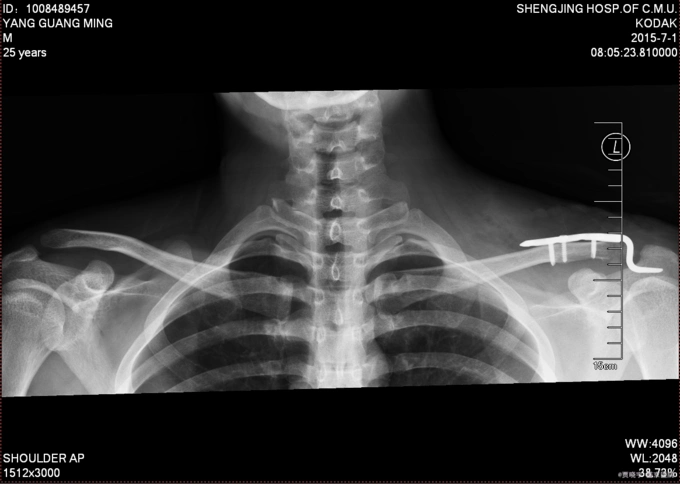

双侧肩胛骨粉碎性骨折合并右侧肩峰骨折

锁骨肩峰端骨折钩板固定